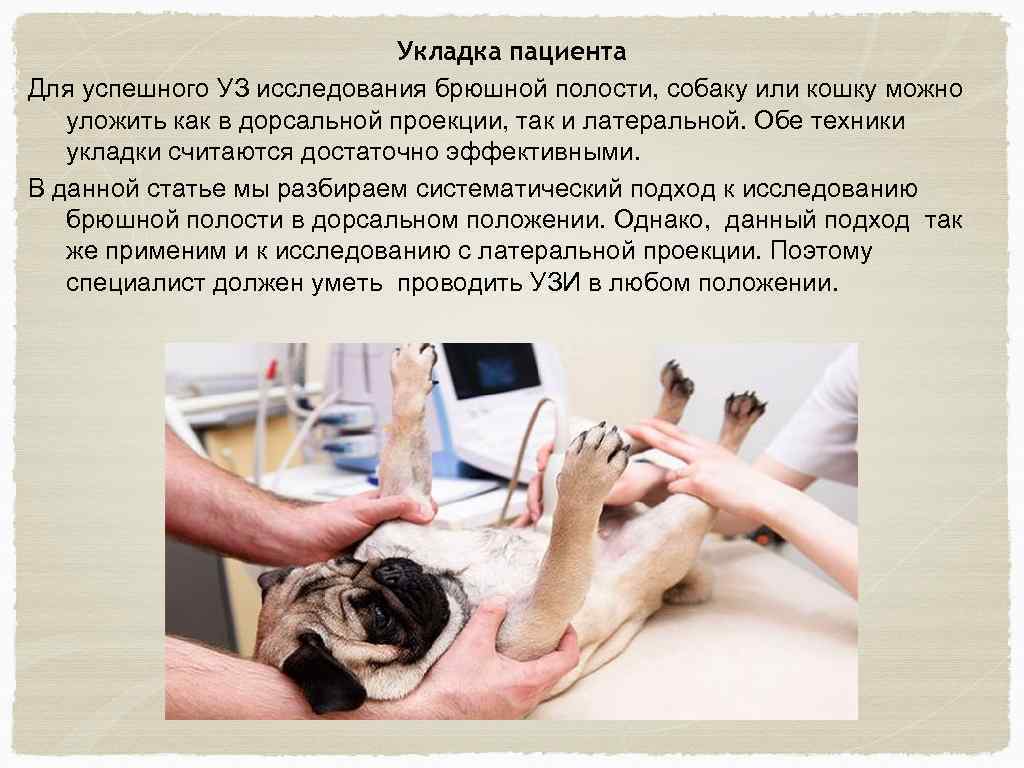

Укладка пациента Для успешного УЗ исследования брюшной полости, собаку или кошку можно уложить как в дорсальной проекции, так и латеральной. Обе техники укладки считаются достаточно эффективными. В данной статье мы разбираем систематический подход к исследованию брюшной полости в дорсальном положении. Однако, данный подход так же применим и к исследованию с латеральной проекции. Поэтому специалист должен уметь проводить УЗИ в любом положении.